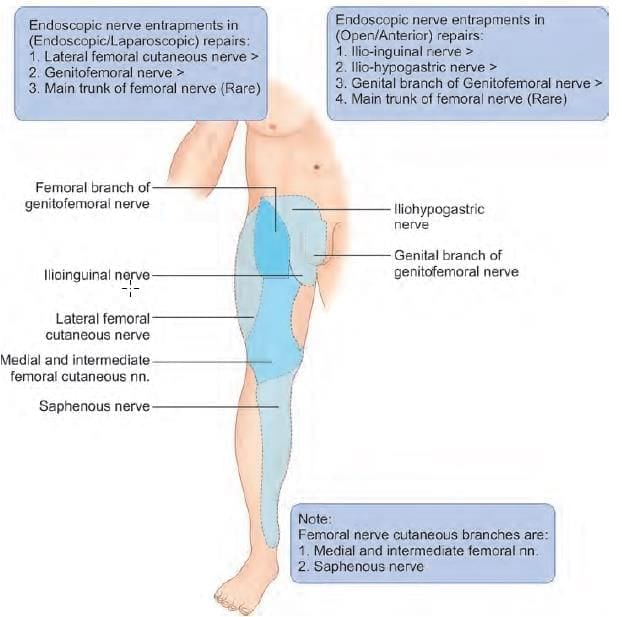

A patient has presented with pain in the right leg region for past 3 months. There is a surgical history of undergoing laparoscopic bilateral inguinal hernia repair. The nerve involved is: (NEET-PG 2023)